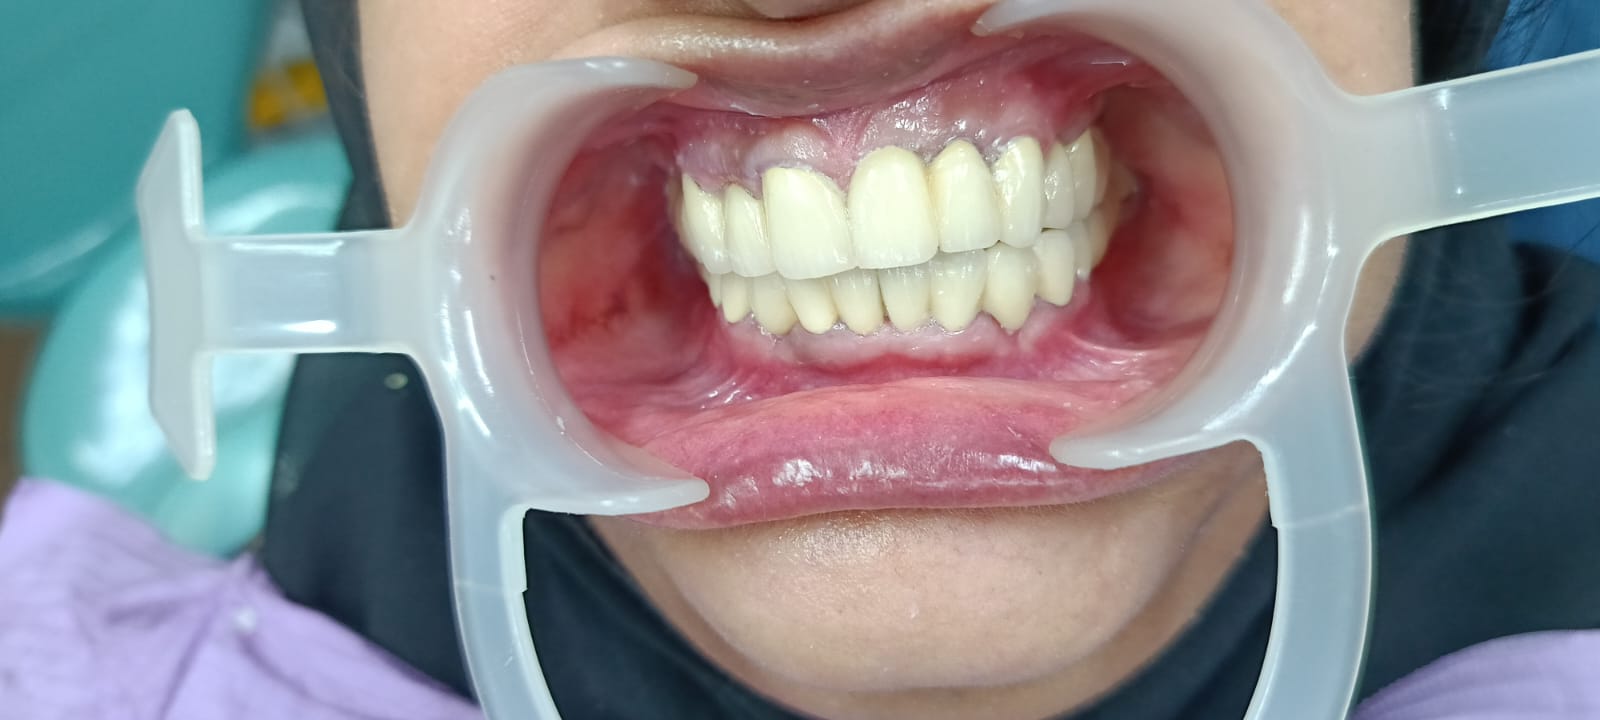

The implant process typically involves several stages, starting with the surgical placement of the implant, followed by a healing period during which the implant fuses with the bone—a process known as osseointegration. After sufficient healing, custom-made crowns are affixed to the implants, restoring both function and natural appearance. This approach allows patients to enjoy improved chewing ability and confidence in their smiles.

Post-implant care is crucial for long-term success, and we provide detailed guidance on maintaining oral hygiene and routine dental visits. Our team is committed to ensuring that patients receive personalized care throughout their implant journey, addressing any concerns and providing support for optimal outcomes. With dental implants, patients can regain their smiles and the ability to enjoy their favorite foods with confidence.